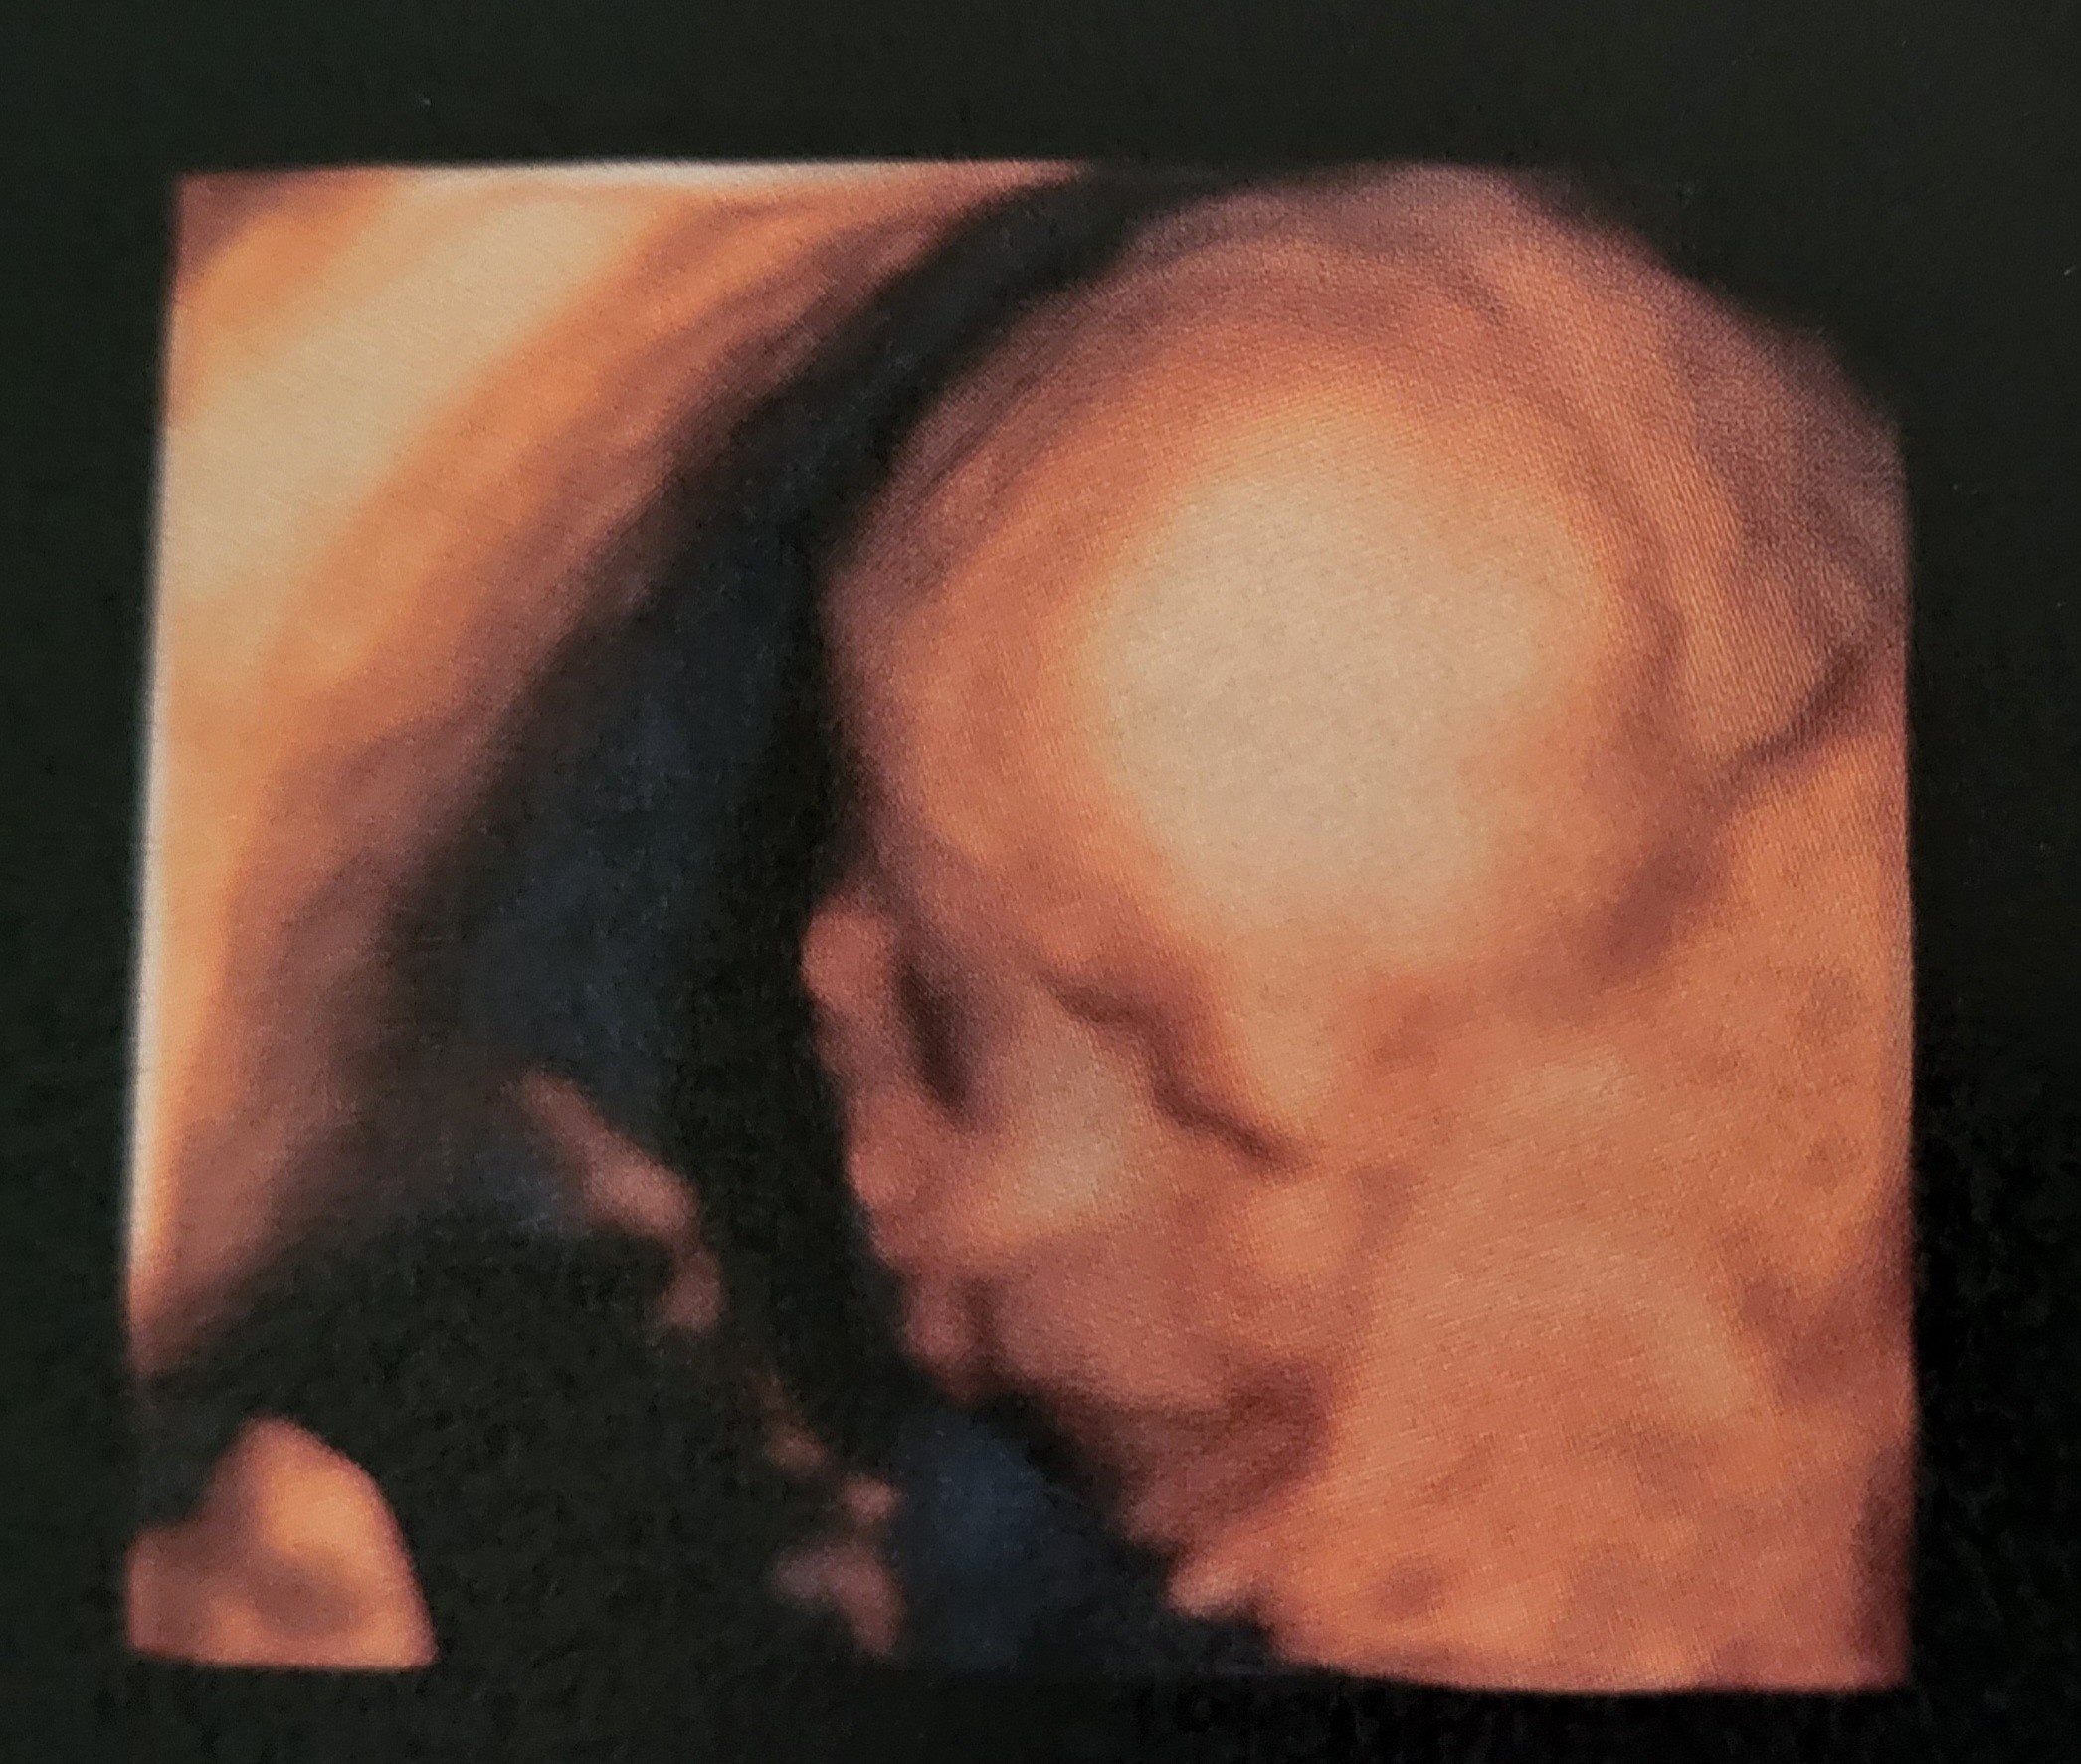

Co oznacza ta wada? Mieliście juz konsultacje z genetykiem?I po usg. Mała waży już 630g.

Następne usg 22.06

Zobacz załącznik 1404780

Przyszly też wyniki amniopunkcji Zobacz załącznik 1404781